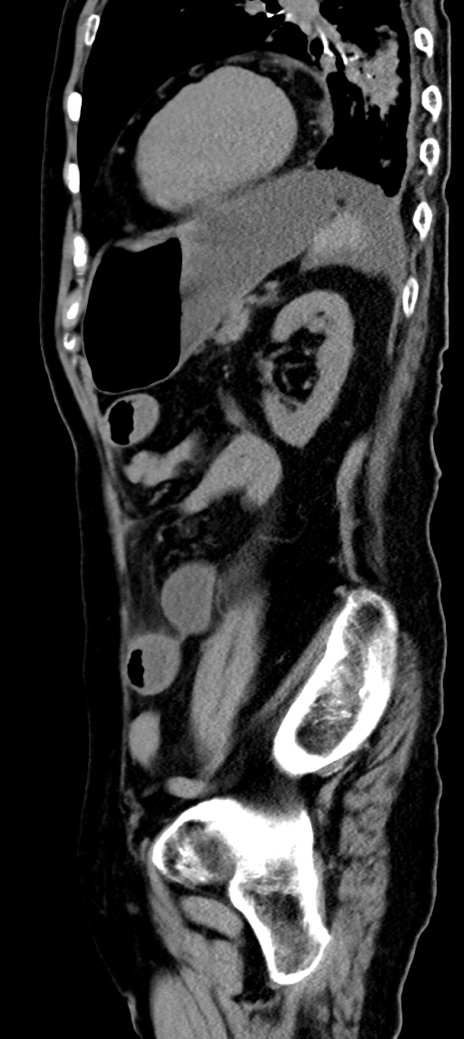

症例40(矢状断像)他院1日前

【症例】90歳代女性

【主訴】腹痛・嘔吐

【現病歴】 食欲低下、嘔吐があり昨日他院受診。肺炎と診断され入院となる。入院後より腹部全体に圧痛あり。胃管留置され経過みていたが、症状持続するため、

当院転院となる。

【既往歴】胸椎圧迫骨折、胆石症

【身体所見】腹部:中央に激痛あり、圧痛あり、反跳痛不明

【データ】WBC 17100、CRP 18.82